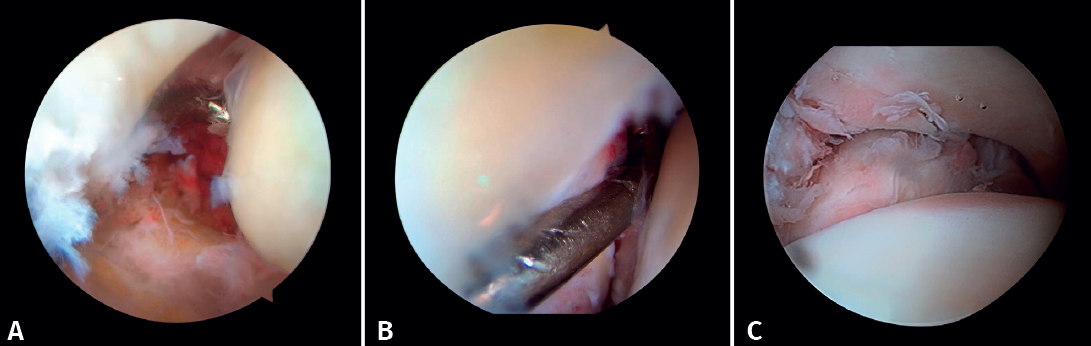

- Diagnóstico de inestabilidad sindesmal: la artroscopia permite la evaluación de la integridad de la sindesmosis y del ECM sobre la radiografía y la TC, sobre todo en la clasificación de las fracturas SER II y IV. Se ha demostrado que la evaluación radiográfica no siempre predice la lesión sindesmal. Además, la artroscopia permite asegurar una reducción anatómica de esta. Takao encontró que el 87% (33/38) de los tobillos con fractura tenían lesiones de la sindesmosis detectadas por artroscopia(20).

La artroscopia permite la visión directa de la sindesmosis y, además, permite su evaluación dinámica(22,21).

- Nos permite diferenciar entre fracturas SER II (en las que no debería existir lesión sindesmal) y fracturas SER IV, en las que sí hay afectación de la sindesmosis, pudiendo estabilizarla(5,23).

- Puede evitar la falsa impresión de un espacio articular medial ensanchado en la fluoroscopia debido a anomalías congénitas.

- Poder visualizar la incisura maleolar junto con el control radioscópico nos permite asegurar un correcto posicionamiento del peroné en la incisura fibularis, sobre todo en las lesiones inestables en las que existe riesgo de mala reducción por acortamiento o rotación del peronéa(5,24).

- Evitar la hipercorrección de la sindesmosis, que es muy artrogénica(5,24) (Figura 6).

Figura 6. A: lesión de sindesmosis; B: control de la reducción para evitar la sobrecorrección; C: control intraoperatorio de la correcta reducción del peroné en la incisura.